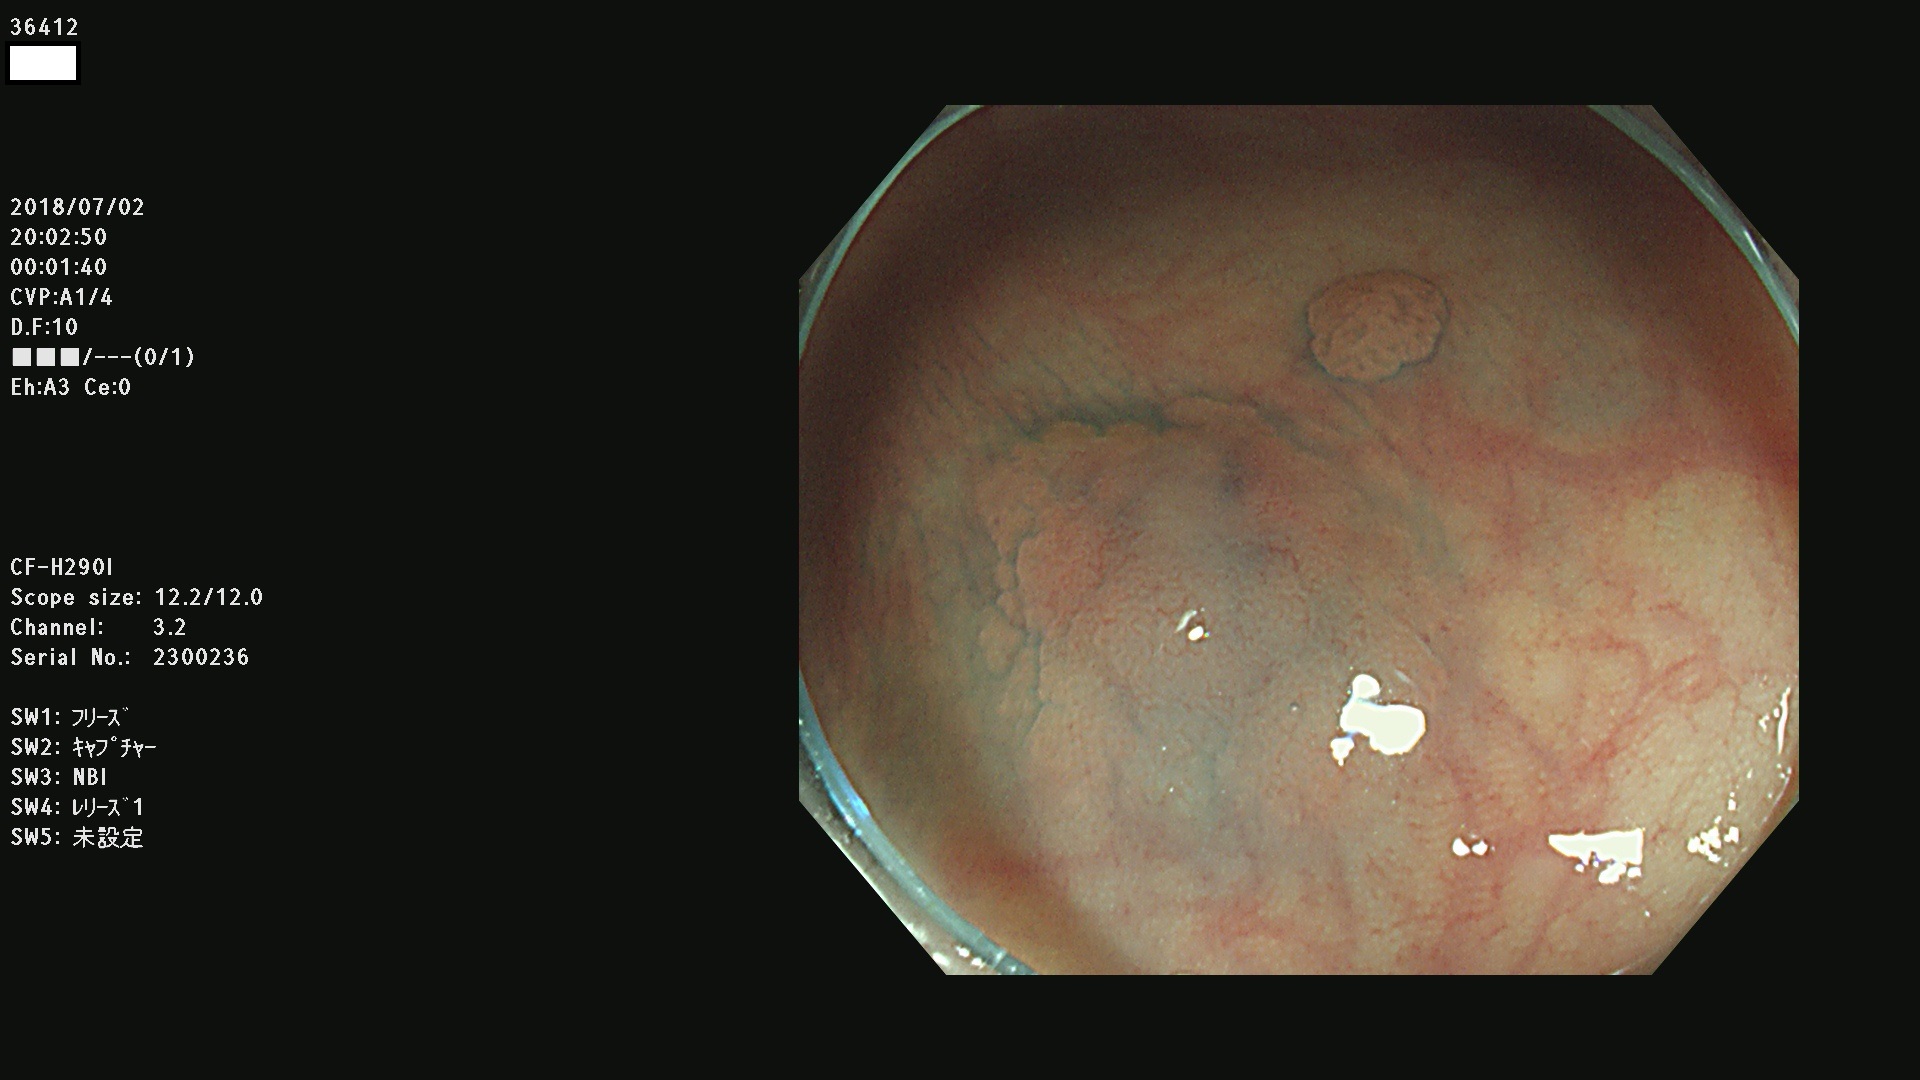

36400(SSAPのみ) 36402 36403 36404 36405 36406 36407 36408(SSAPのみ) 36412 36413 36414 36415 36416 36417 36418 36420 36422 36423 36424 36425 36426 36428 36429 36430 36431 36434 36435 36436 36437 36438 36440 36443 36447 36448 36449 36450 36452 36454 36458 36459 36460 36462(SSAPのみ) 36463 36464 36465 36466 36470 36471 36472 36473 36474 36475 36476 36478 36480 36481 36482 36484 36487 36488 36489 36490 36492 36494 36495 36496 36497 36498

発見困難で危険性の高い平坦型病変(上記100名より抽出)